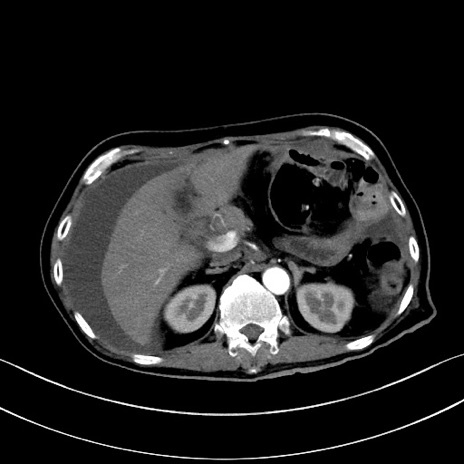

症例28(横断像)

【症例】60歳代男性

【主訴】嘔吐

【現病歴】胃癌にて胃全摘後。食思不振が悪化し、夜中に嘔吐することがある。

【既往歴】胃癌、胃全摘、脾摘、胆摘後

【データ】WBC 5900、CRP 10.56